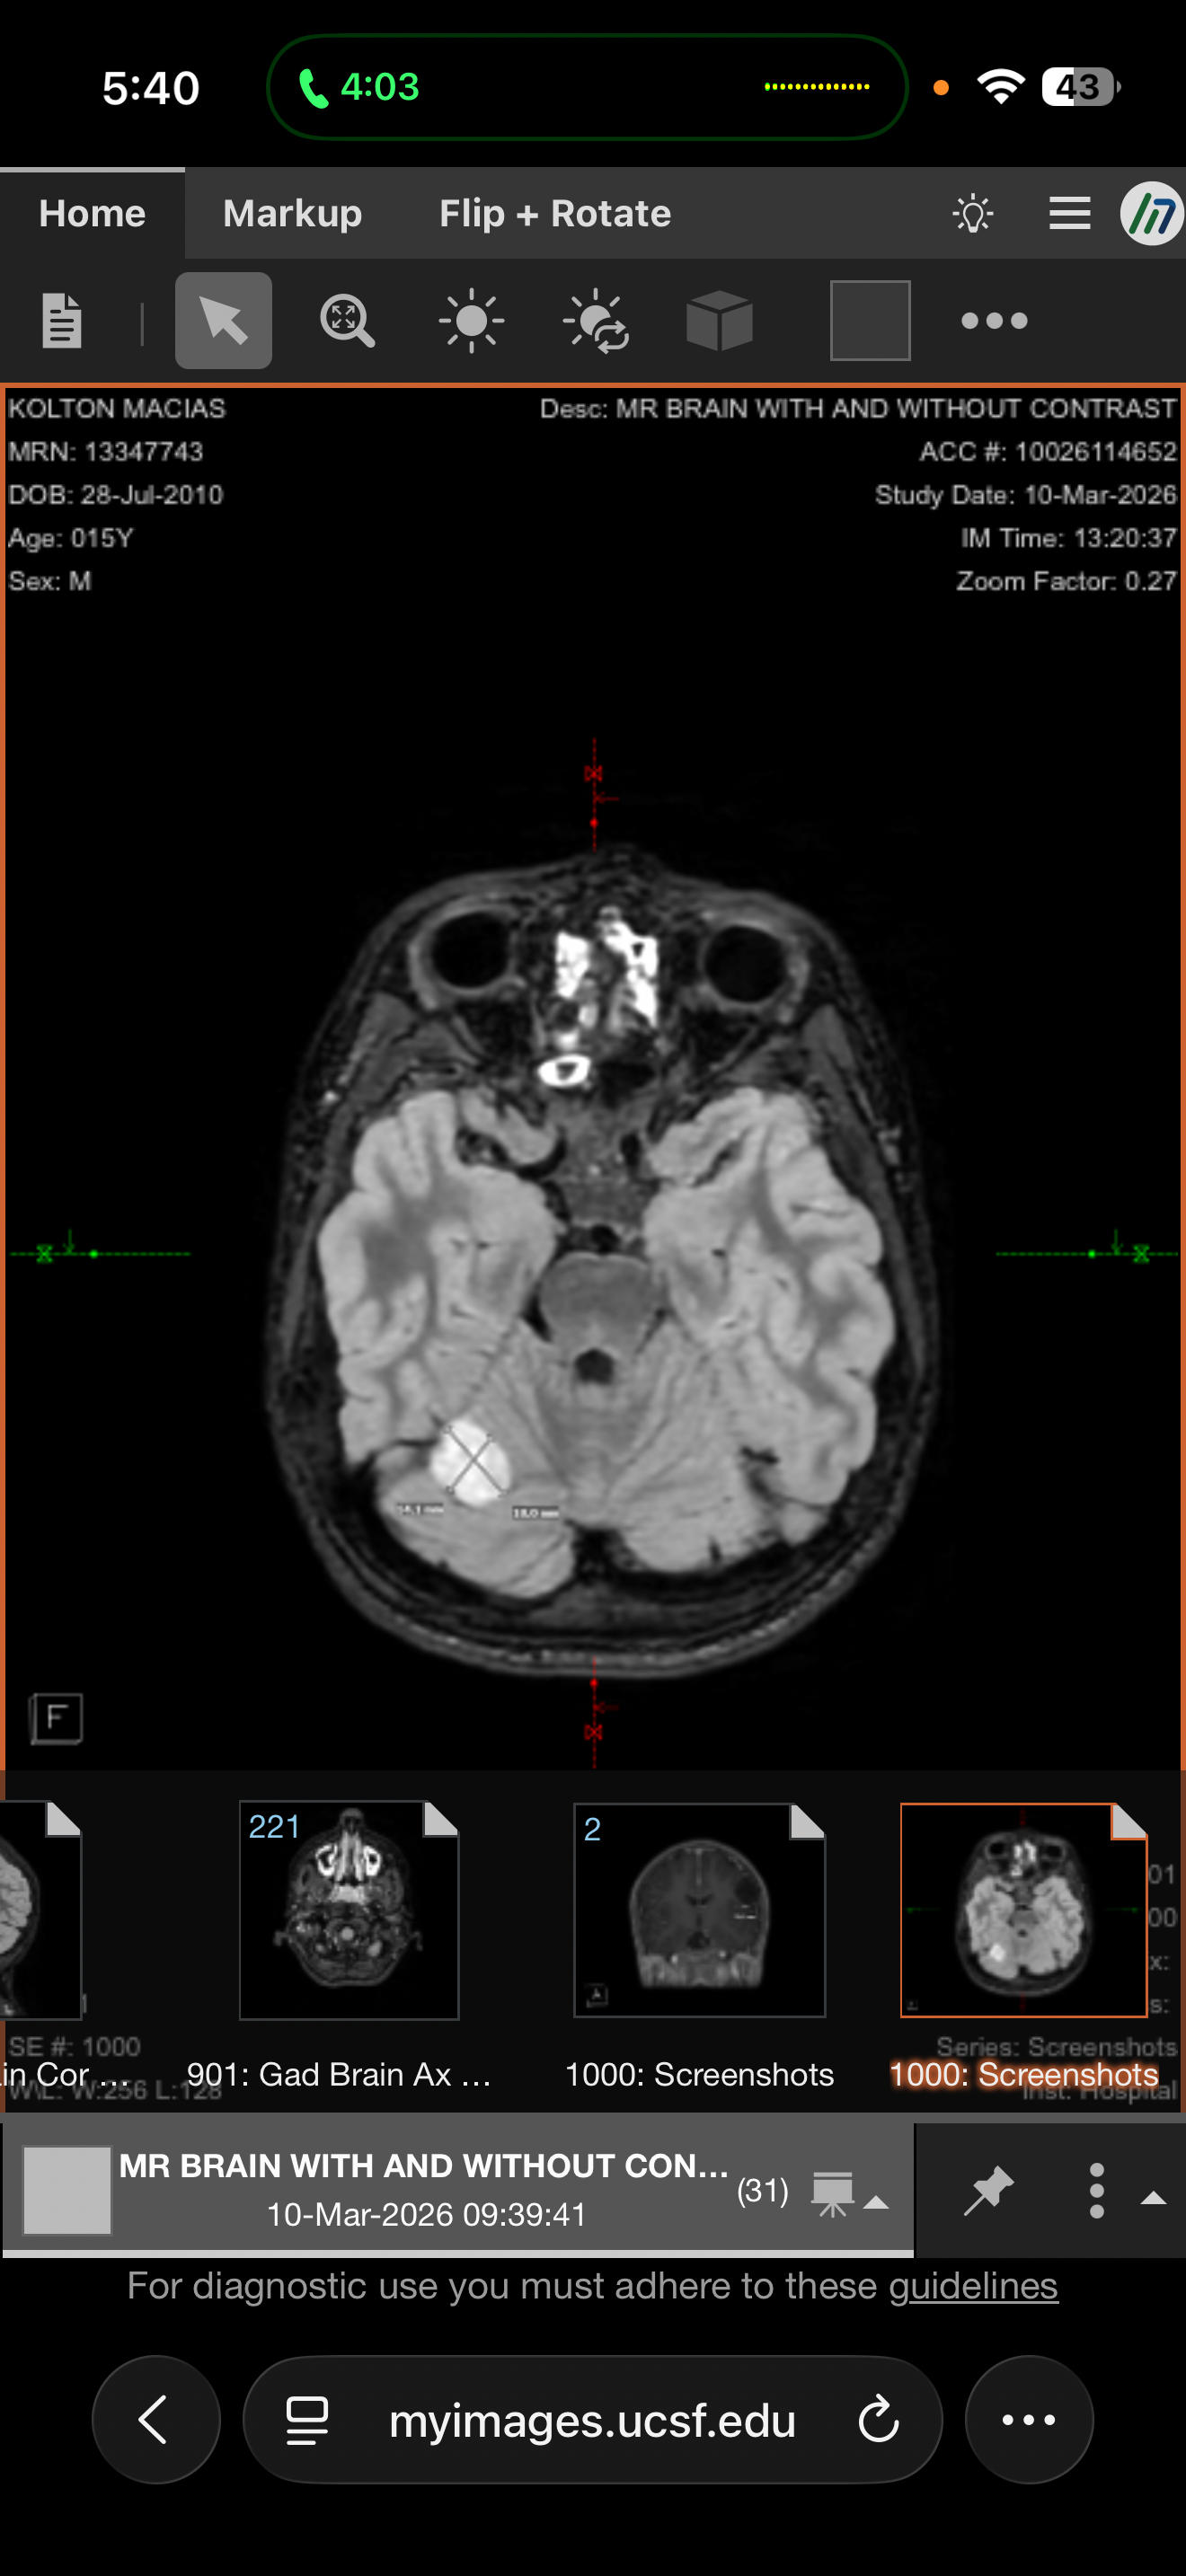

Our hearts are heavy as we share that Kolton has recently been diagnosed with multiple brain tumors. After urgent evaluations, doctors discovered four tumors, including one located in the cerebellum. At this time, Kolton’s medical team is moving forward with a biopsy and laser ablation procedure to treat one of the tumors. The remaining tumors are expected to be managed with oral medications and ongoing treatment. This journey will require frequent monitoring, including MRIs every 3 months, and close follow-up with specialists.